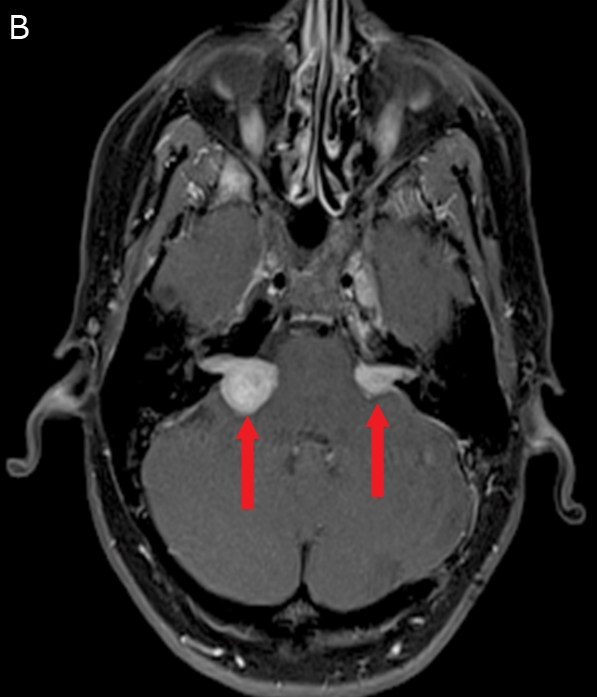

NF1

The MRI image above shows bilateral tumors at the cerebellopontine angle (arrows). Most intracranial schwannomas are found at the cerebellopontine angle and are attached to CN VIII. Schwannomas at this location are called acoustic neuromas. Tinnitus, vertigo, and hearing loss are the typical symptoms of an acoustic neuroma. Bilateral acoustic neuromas occur in neurofibromatosis (NF) type 2. NF-2 differs from NF-1 in that it causes fewer cutaneous manifestations and presents with central nervous system involvement.

Both types of neurofibromatosis are autosomal dominant conditions, although they occur due to mutations on different chromosomes. The difference between these 2 diseases is summarized below.